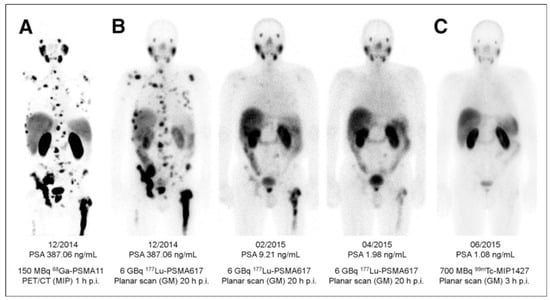

PSMA PET has demonstrated strong impact on therapy planning and clinical decision making with treatment regimen adjustment in 27%–77% of patients [136,137,138,139,140,141,142,143,144]. The most frequently used pair in the context of radiotheranostics is [68Ga]Ga-PSMA-11 and [177Lu]Lu-PSMA-617 (Figure 7). Despite the structural difference and various radionuclides, it was demonstrated that [68Ga]Ga-PSMA-11 PET plays an important role in predicting treatment response to [177Lu]Lu-PSMA-617 and monitoring response for patient treatment management optimization [131,145,146,147,148]. Phase II prospective clinical trial demonstrated correlation of the treatment response with the uptake of [68Ga]Ga-PSMA-11 (Figure 8) [146]. Encouraging results in terms of safety, efficiency, response rate, toxicity, and reduction of pain have been demonstrated by clinical trials assessing the role of [177Lu]Lu-PSMA-617 in patients with mCRPC (Figure 9) [131,132,149,150].

Figure 9.

(A) Pre-therapeutic imaging using [68Ga]Ga-PSMA-11 PET/CT delivering highest resolution; (B) Co-emission of γ-rays by Lu-177 enables imaging during therapy with [177Lu]Lu-PSMA-617; (C) 99mTc-PSMA scintigraphy has minimally less noise than posttherapy scanning and can be used for imaging follow-up in out-patient setting. GM 5 geometric mean; MIP 5 maximum-intensity projections; p.i. 5 after injection. Reproduced from [132].